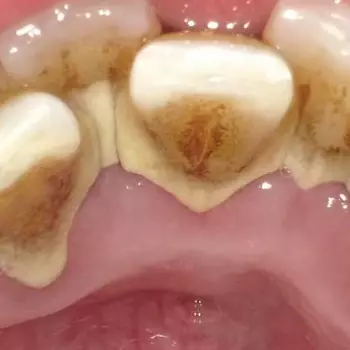

치석 이란, 치구(플라크)와 타액에 포함된 인산이나 칼슘, 음식물 찌꺼기 등이 결합해 치아에 달라붙어 석회화된 것입니다.

치석은 약 80%가 인산칼슘이고 그 외에 단백질이나 탄수화물, 세균의 시체, 음식물 찌꺼기 등이 포함되어 있습니다.

치석은 이름처럼 돌처럼 단단하므로 일반 칫솔질로는 제거가 불가능하며, 치석을 제때 제대로 제거하지 않으면 증상이 악화되어 치은염이나 치주염으로 발전될 수 있으니 적절히 케어해야 합니다.

구강 내의 세균과 인산, 칼슘, 음식물 찌꺼기 등의 결합물인 치석은 플라크와 결합하여 치아 표면의 치석 형성을 촉진시킵니다.

올바르지 못한 칫솔질 방법과 탄산음료와 같은 과도한 당의 섭취, 고르지 않은 치아 배열은 치석 형성을 촉진할 수 있으며, 치주 질환이나 구강 건강에 문제가 있을 경우에는 치석이 더 쉽게 발생할 수 있습니다.